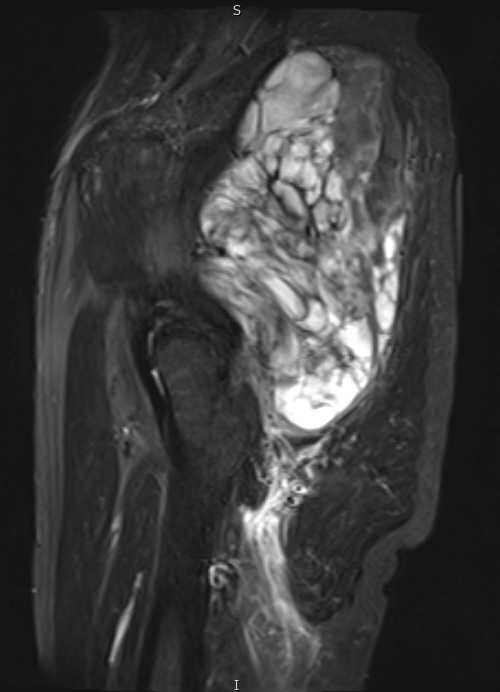

Fig. 6 STIR MR image demonstrates a large mass in the gluteal region with some enhancing tissue posterior to the trochanteric area which may reflect reactive edema.

Fig. 7 & 8 Magnetic Resonance Image shows a large heterogeneous mass in the right thigh with low intensity signal on Axial (Fig. 7) and Coronal (Fig. 8) T1-weighted images admixed with high signal areas. The high signal areas represent low grade fatty tissue and low signal the dedifferentiated areas. Higher intensity signal is visible compatible with hemorrhage or necrotic tissue.

Fig. 9 Coronal fat suppressed T1-weigthed MR image demonstrates a large heterogeneous mass in the anterior compartment of the thigh with some areas suppressed corresponding with fatty areas within the tumor. Central hyper enhanced areas compatible with hemorrhage or necrosis.

Fig. 10 Axial T2 weighted MR image demonstrates a large well encapsulated heterogeneous mass with multiple thick internal trabeculations located in the anterior compartment of the thigh.

Fig. 11 – 13 Axial (Fig. 11), Coronal (Fig. 12) and Sagital (Fig. 13) contrasted T1-weighted MR images show a large heterogeneous mass with central and peripheral

enhancement. Multiple thick trabeculations. Central low signal intensity image is compatible with necrosis and hemorrhage.